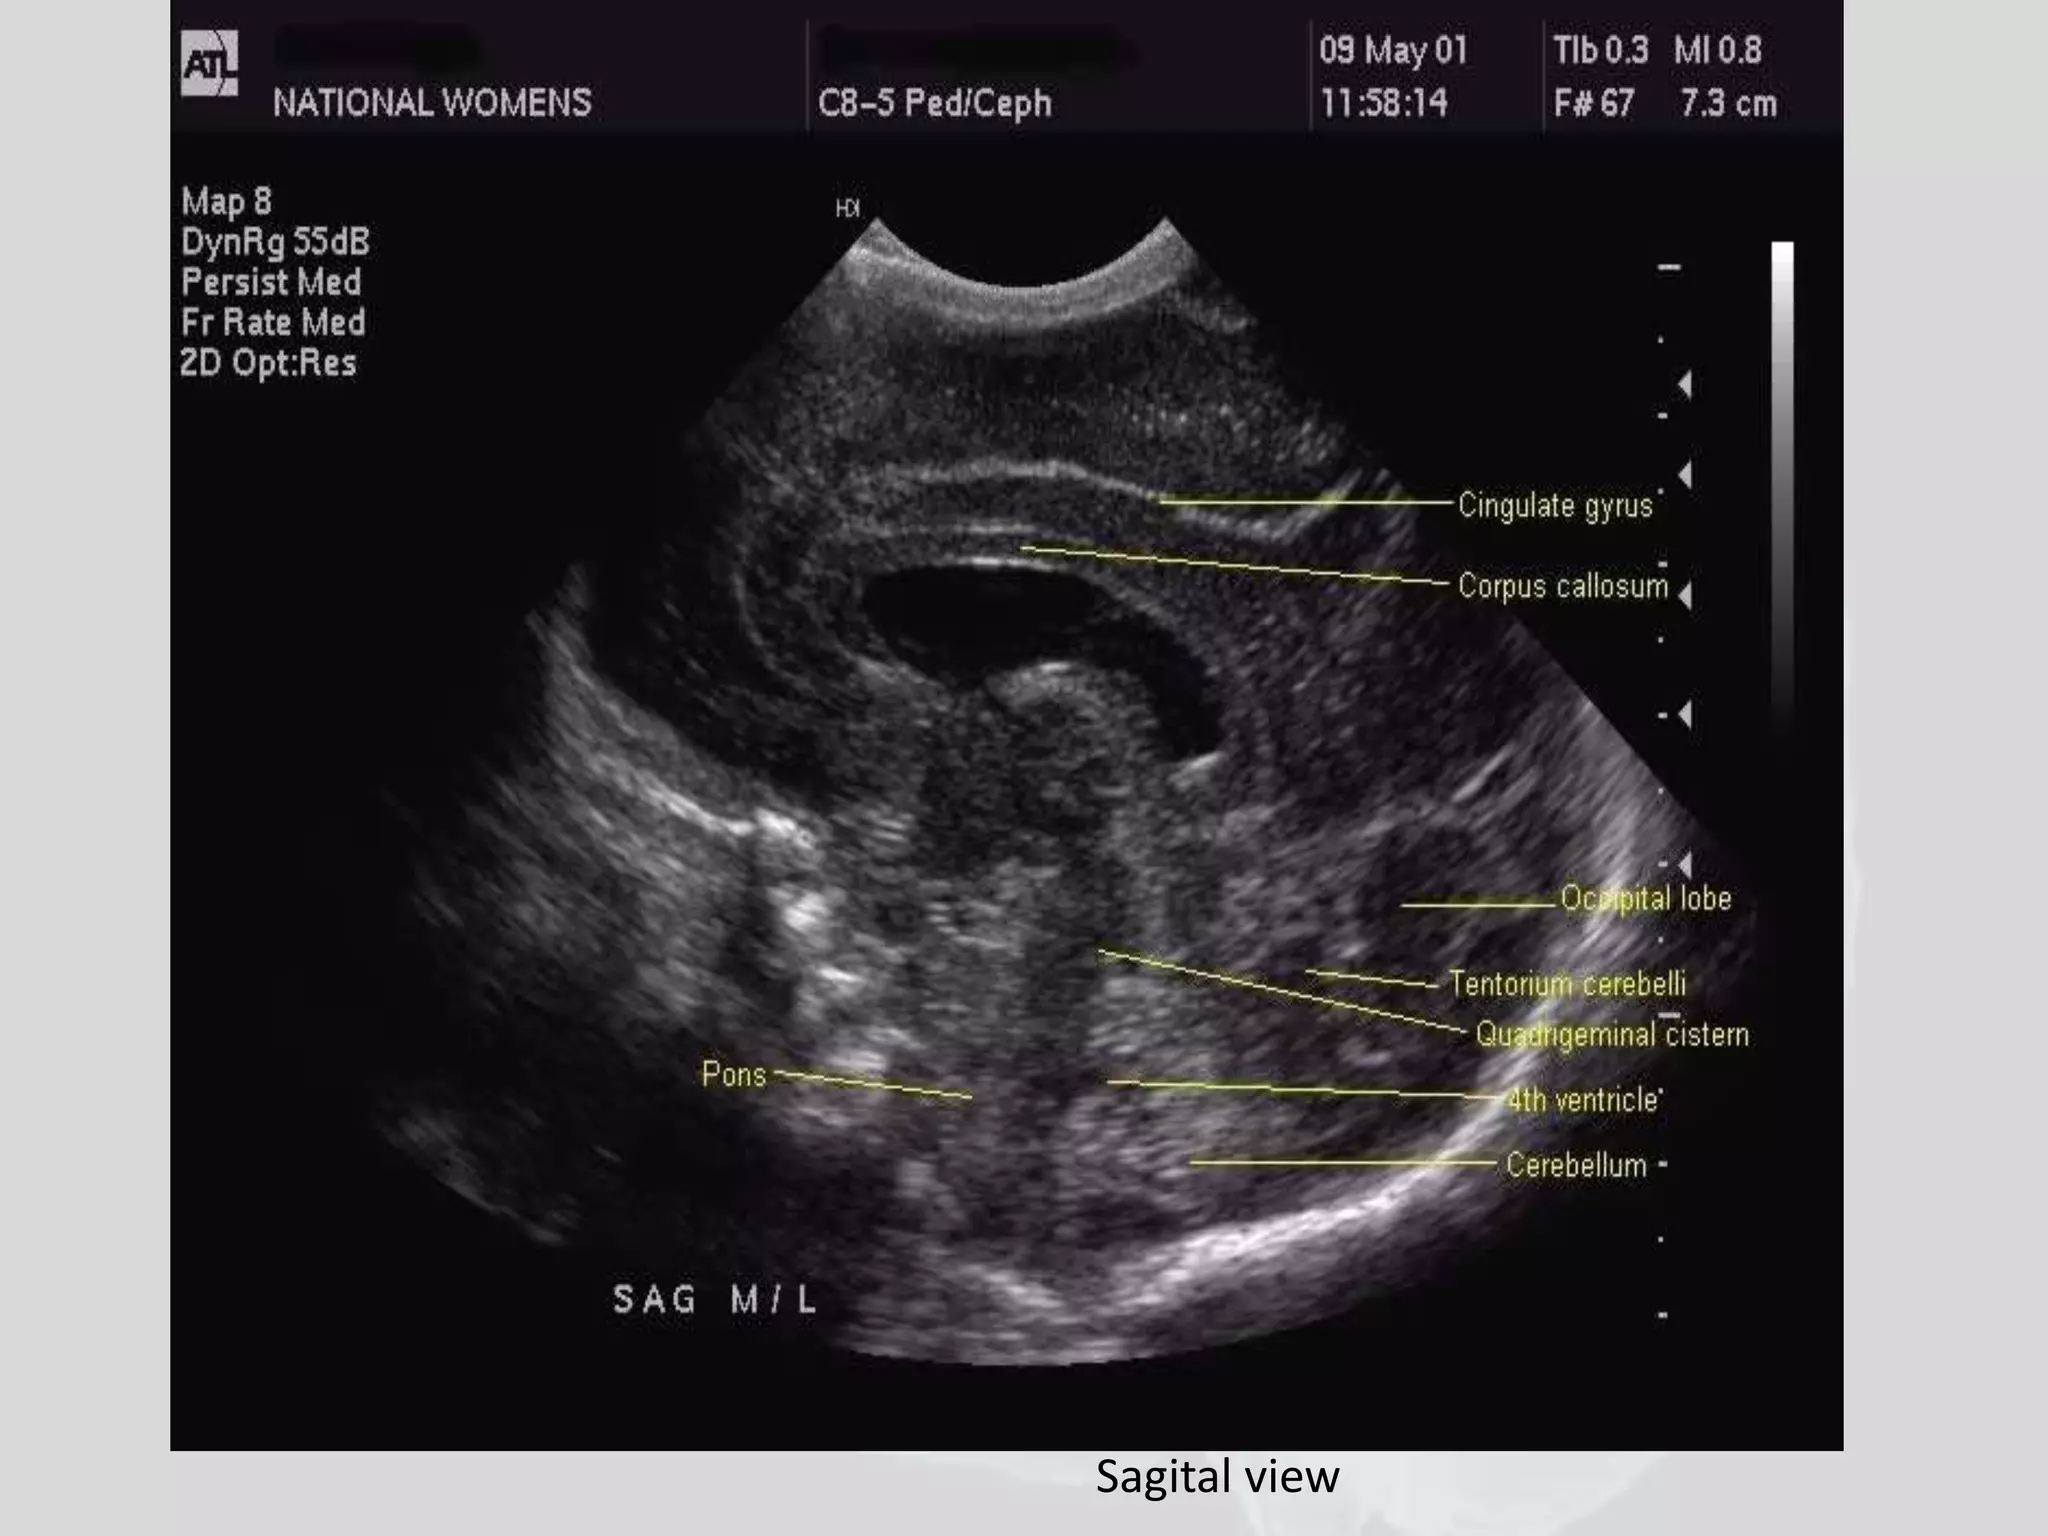

• In the sagittal images check the caudothalamic

grooves for signs of hemorrhage, check the

midline for the corpus callosum and the

cerebellum

Cranial usg

Sagital view